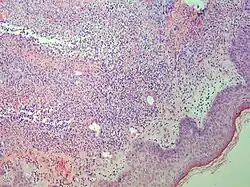

Punch biopsy of a skin lesion showing neutrophilic infiltration in the dermis, with no evidence of vasculitis (same patient with Crohn's disease).

Studies show a moderate neutrophilia (less than 50%), elevated ESR (greater than 30 mm/h) (90%), and a slight increase in alkaline phosphatase (83%). Skin biopsy shows a papillary and mid-dermal mixed infiltrate of polymorphonuclear leukocytes with nuclear fragmentation and histiocytic cells. The infiltrate is predominantly perivascular with endothelial-cell swelling in some vessels, but vasculitic changes (blood clots; deposition of fibrin, complement, or immunoglobulins within the vessel walls; red blood cell extravasation;inflammatory infiltration of vascular walls) are absent in early lesions.Perivasculitis occurs secondarily, because of cytokines released by the lesional neutrophils. True transmural vasculitis is not an expected finding histopathologically in SS.